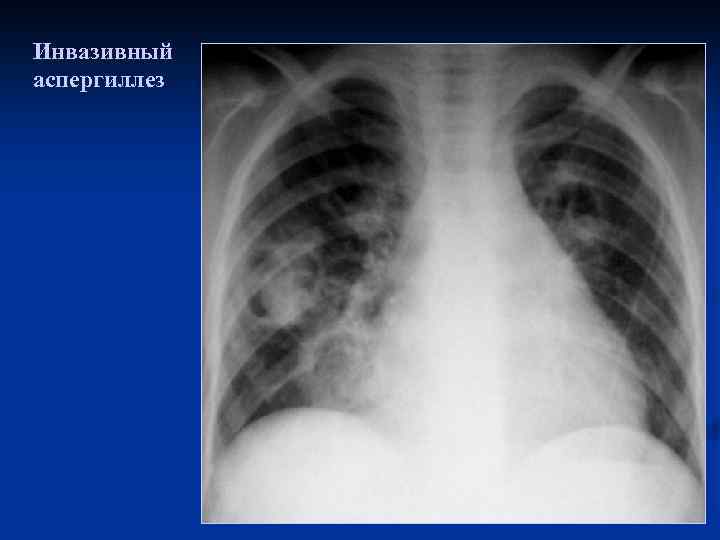

Инвазивный аспергиллез

Инвазивный аспергиллез